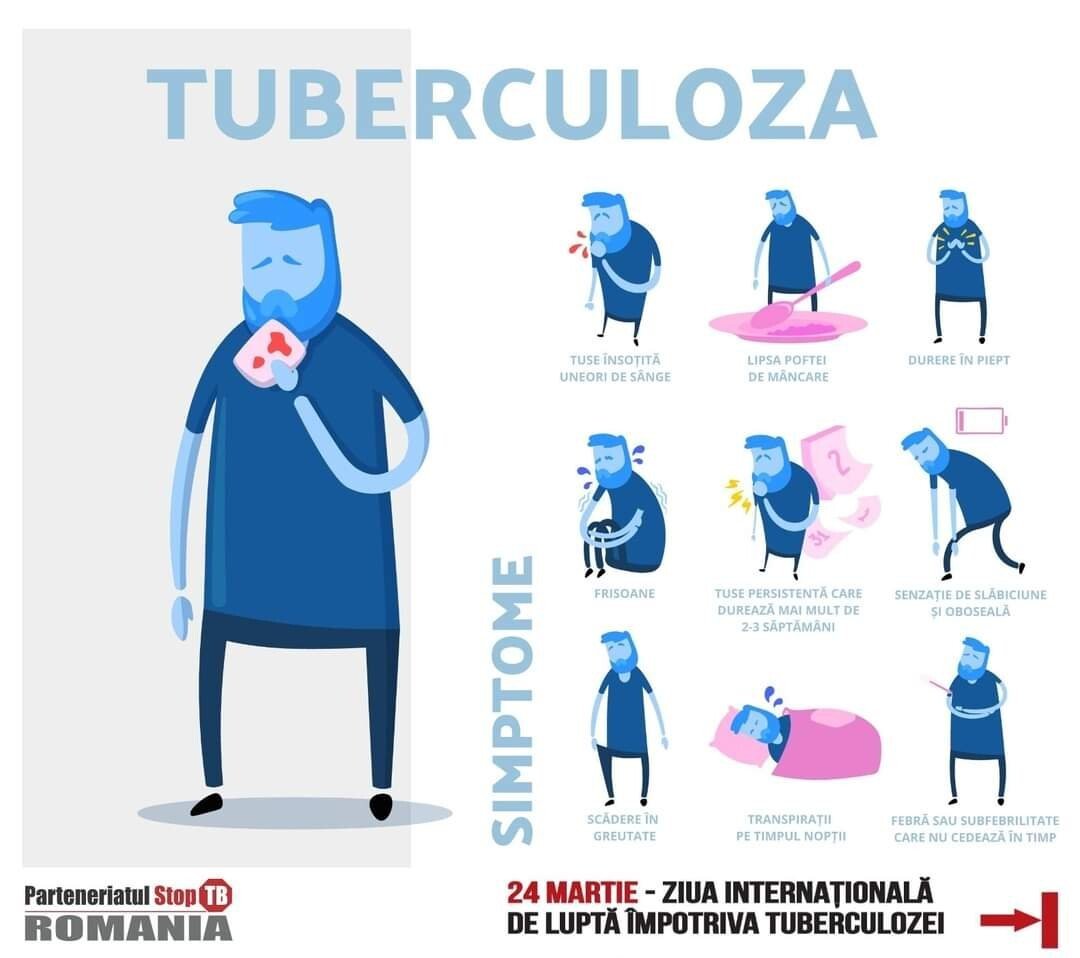

Semnele obișnuite ale tuberculozei pulmonare sunt:

• tusea persistentă care durează mai mult de 2-3 săptămâni, însoțită uneori de flegmă (spută) cu sânge și durere în piept

• febră sau subfebrilitate care nu cedează în timp

• transpirații pe timpul nopții

• lipsa poftei de mâncare

• scăderea în greutate

• senzația de slăbiciune și de oboseală

• astenie

• umflături în zona gâtului, la subraț sau în vintre (zona abdomenului)

• insomnie

• nervozitate.